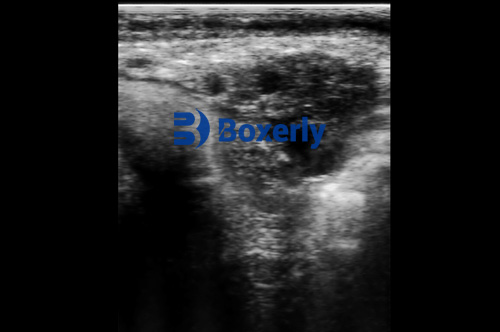

Veterinary ultrasound is a diagnostic imaging technique that uses high-frequency sound waves to produce real-time images of internal body structures. It is widely used in livestock for pregnancy diagnosis, evaluation of reproductive organs, and assessing soft-tissue injuries or diseases.

Pregnancy checks are among the most common uses of ultrasound in cattle. With portable ultrasound machines and a trained technician, experienced veterinarians can assess pregnancies very quickly—often under 5 minutes per cow. If the fetus is small and early in gestation, scanning may be even faster.Reproductive Tract Evaluation: 5–10 minutes per animal

When scanning the uterus and ovaries to monitor ovulation, detect cysts, or evaluate fertility issues, the exam takes longer. Each structure needs to be visualized from multiple angles, requiring more time and precision.Small Ruminants (Sheep & Goats): 2–4 minutes per animal

In ewes and does, pregnancy detection is typically done between 40–90 days of gestation. Ultrasound is fast and effective in these animals, especially using a transabdominal approach with a linear or convex probe.Swine (Pigs): 1–3 minutes per animal

Ultrasound is most commonly used to confirm pregnancy in sows around 21–30 days post-breeding. The process is very brief, especially in commercial settings using high-frequency transducers optimized for swine anatomy.Soft Tissue or Musculoskeletal Injury Evaluation: 10–20 minutes per animal

If the exam is for a lameness evaluation or internal soft tissue injury (e.g., liver, kidney, spleen, muscle), the procedure is more extensive. The veterinarian will need to scan multiple anatomical areas and may perform image measurements or Doppler flow studies.